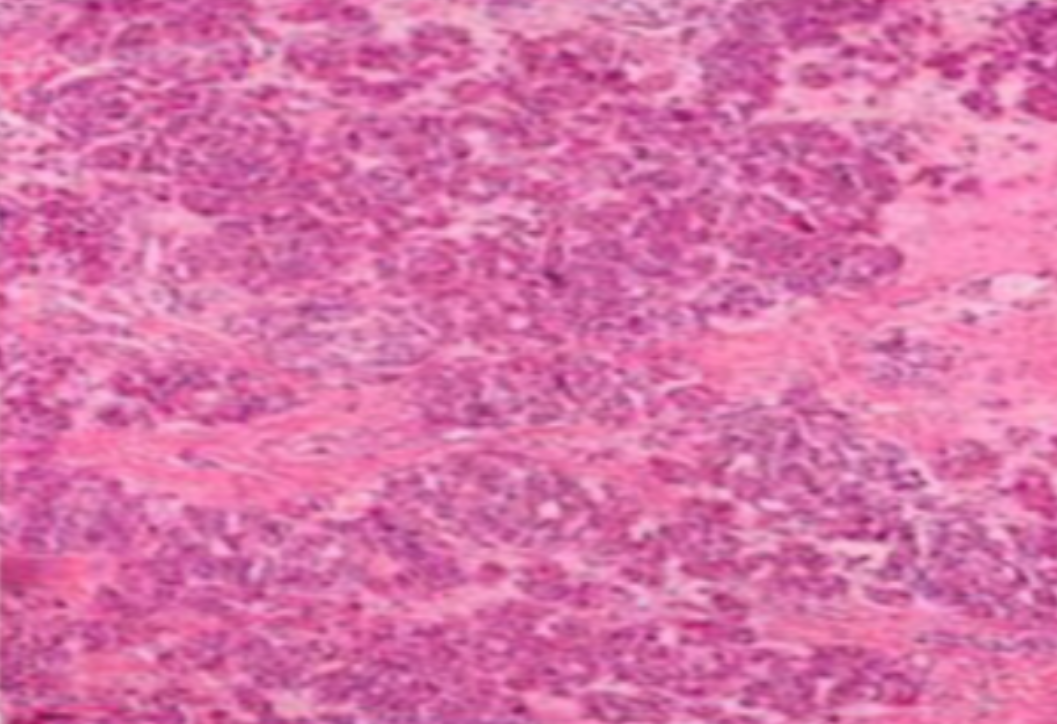

HE染色,全称苏木精-伊红染色法(Hematoxylin and Eosin staining),是最常见的组织切片染色技术之一,用于在显微镜下观察和分析组织或细胞的结构和形态。

虽然HE染色是最常见且最基础的染色技术之一,😭但在实验过程中,很容易出现各种情况导致染色切片质量参差不齐。所以,小编根据以往实验经验,给大家整理归纳出了15个HE染色中的常见问题,还包含问题原因分析以及解决方法哦~